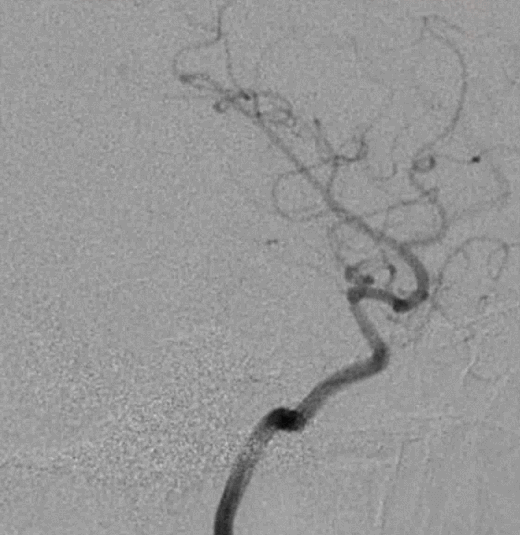

术后3月余复查:血管重塑良好,狭窄及动脉瘤均较前改善

术前                         术后3个月

术后3月复查,瘤体未见显影,载瘤动脉通畅

术后4月余随访:多发动脉瘤均未见显影,远端残余轻度狭窄